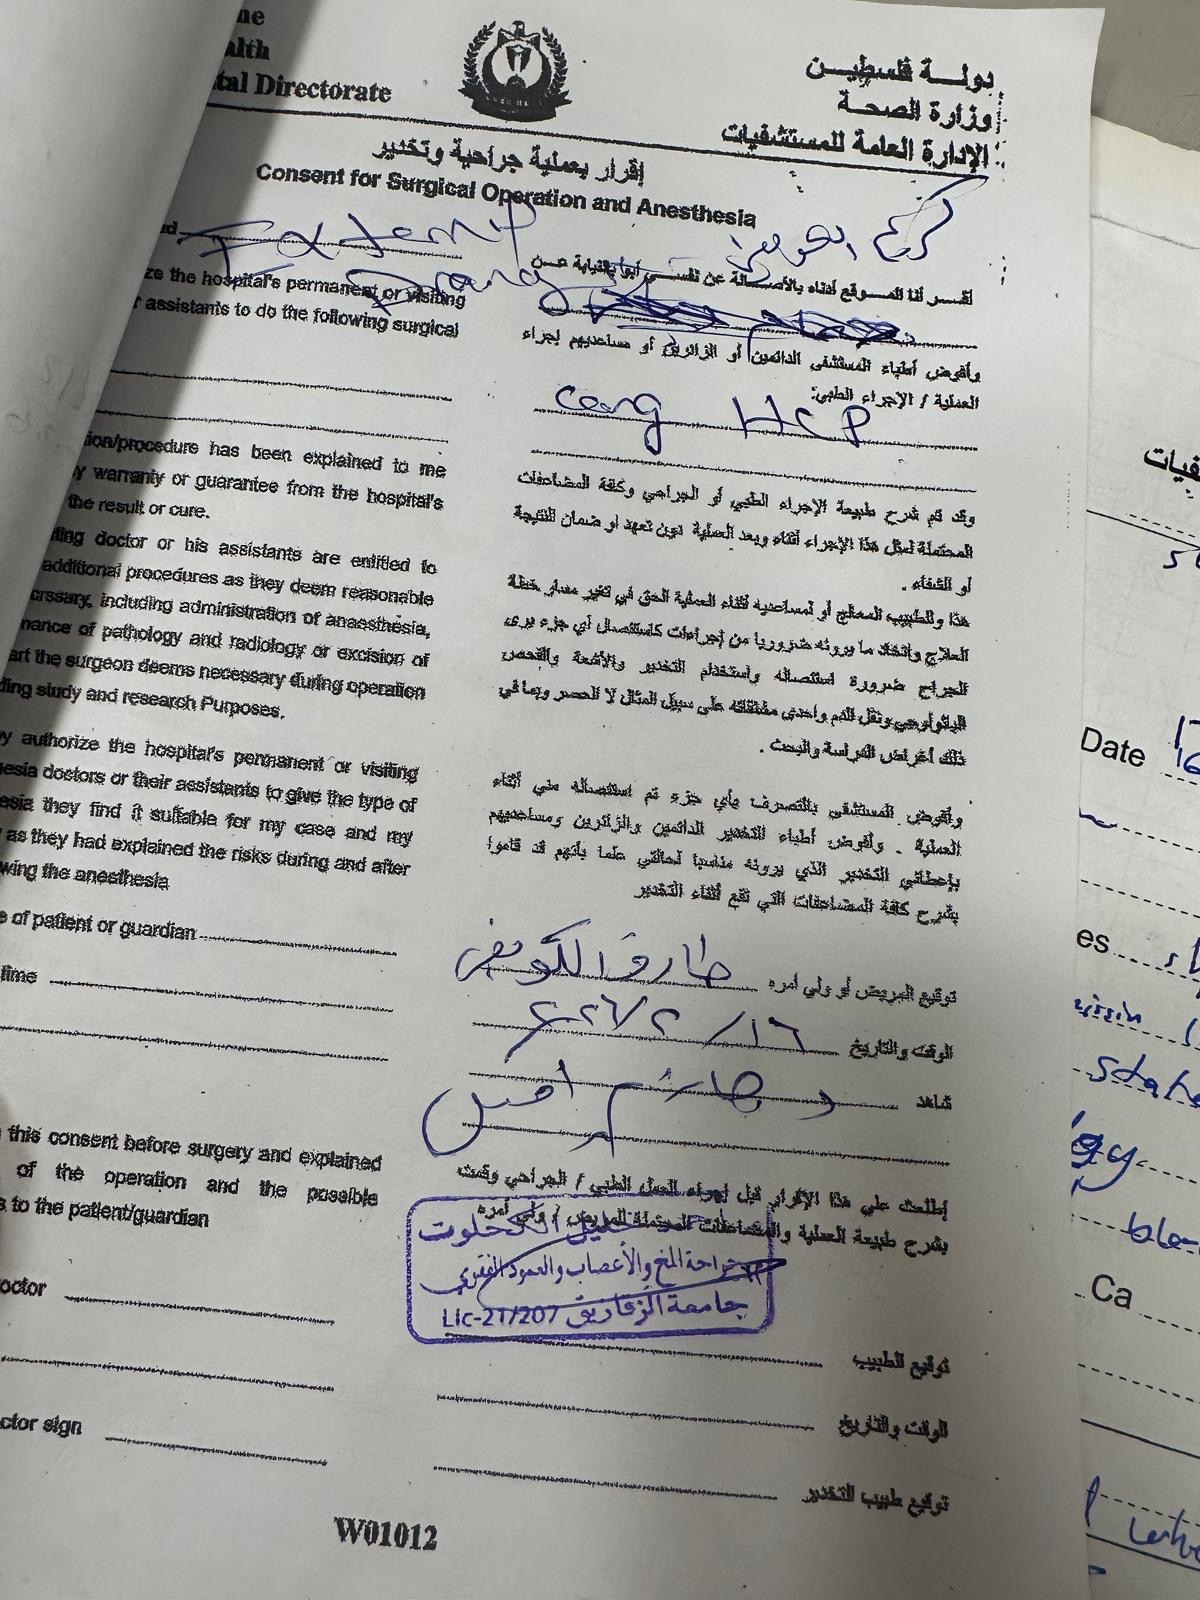

Doctors have outlined an initial urgent treatment plan.

The first stage requires three specialized medical injections to stimulate body and height growth as part of stabilizing his overall development.

Due to the extreme urgency of this child’s condition, we have made the painful decision to prioritize his medical evacuation and life-saving treatment. All remaining support will be used for:

• Emergency medical transfer

• Specialized neurological care

• Hospitalization and essential follow-up treatment

• The first stage injections required to begin stabilizing his condition